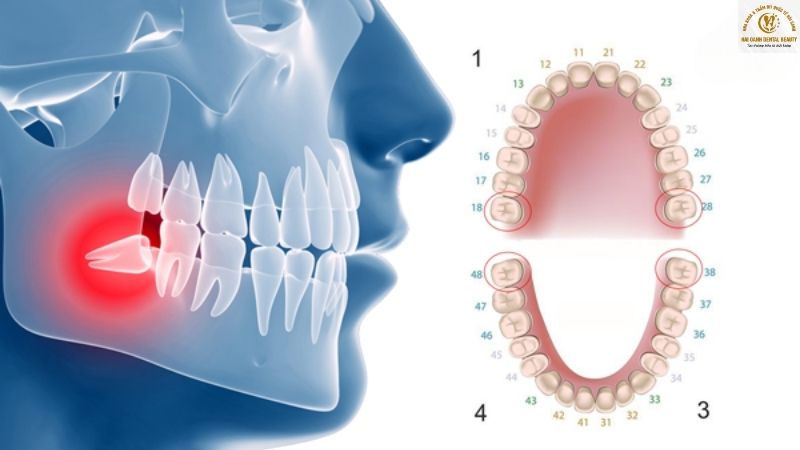

Thông thường, một người có đủ bộ răng vĩnh viễn là 32 chiếc, bao gồm 28 răng thông thường và thêm 4 chiếc răng khôn. Bốn chiếc răng khôn này, hay còn gọi là răng số 8, nằm ở vị trí cuối cùng của cung hàm, mỗi chiếc ở một góc phần tư (trên-trái, trên-phải, dưới-trái, dưới-phải). Chúng thường mọc sau 28 chiếc răng còn lại.

Ảnh minh hoạ cung hàm răng của chúng ta

Vấn đề phát sinh khi răng khôn mọc lên là do xương hàm của con người ngày càng nhỏ lại, không còn đủ chỗ cho chiếc răng cuối cùng này. Khi thiếu không gian, răng khôn không thể mọc thẳng theo hướng bình thường mà sẽ có xu hướng tìm cách mọc lệch, gây ra nhiều biến chứng nguy hiểm. Dưới đây là các kiểu mọc lệch phổ biến:

- Mọc thẳng nhưng không đủ chỗ: Răng khôn mọc thẳng nhưng bị kẹt lại dưới nướu hoặc một phần nướu che phủ, gây đau nhức và khó vệ sinh.

- Mọc nghiêng: Răng khôn mọc lệch và đâm thẳng vào răng số 7 (răng hàm lớn thứ hai) ngay bên cạnh. Tình trạng này có thể gây tổn thương, sâu răng hoặc xô lệch các răng khác.

- Mọc ngầm: Răng khôn nằm hoàn toàn dưới nướu và xương hàm, không thể nhú lên được. Răng ngầm có thể gây đau âm ỉ, u nang và ảnh hưởng nghiêm trọng đến xương hàm.